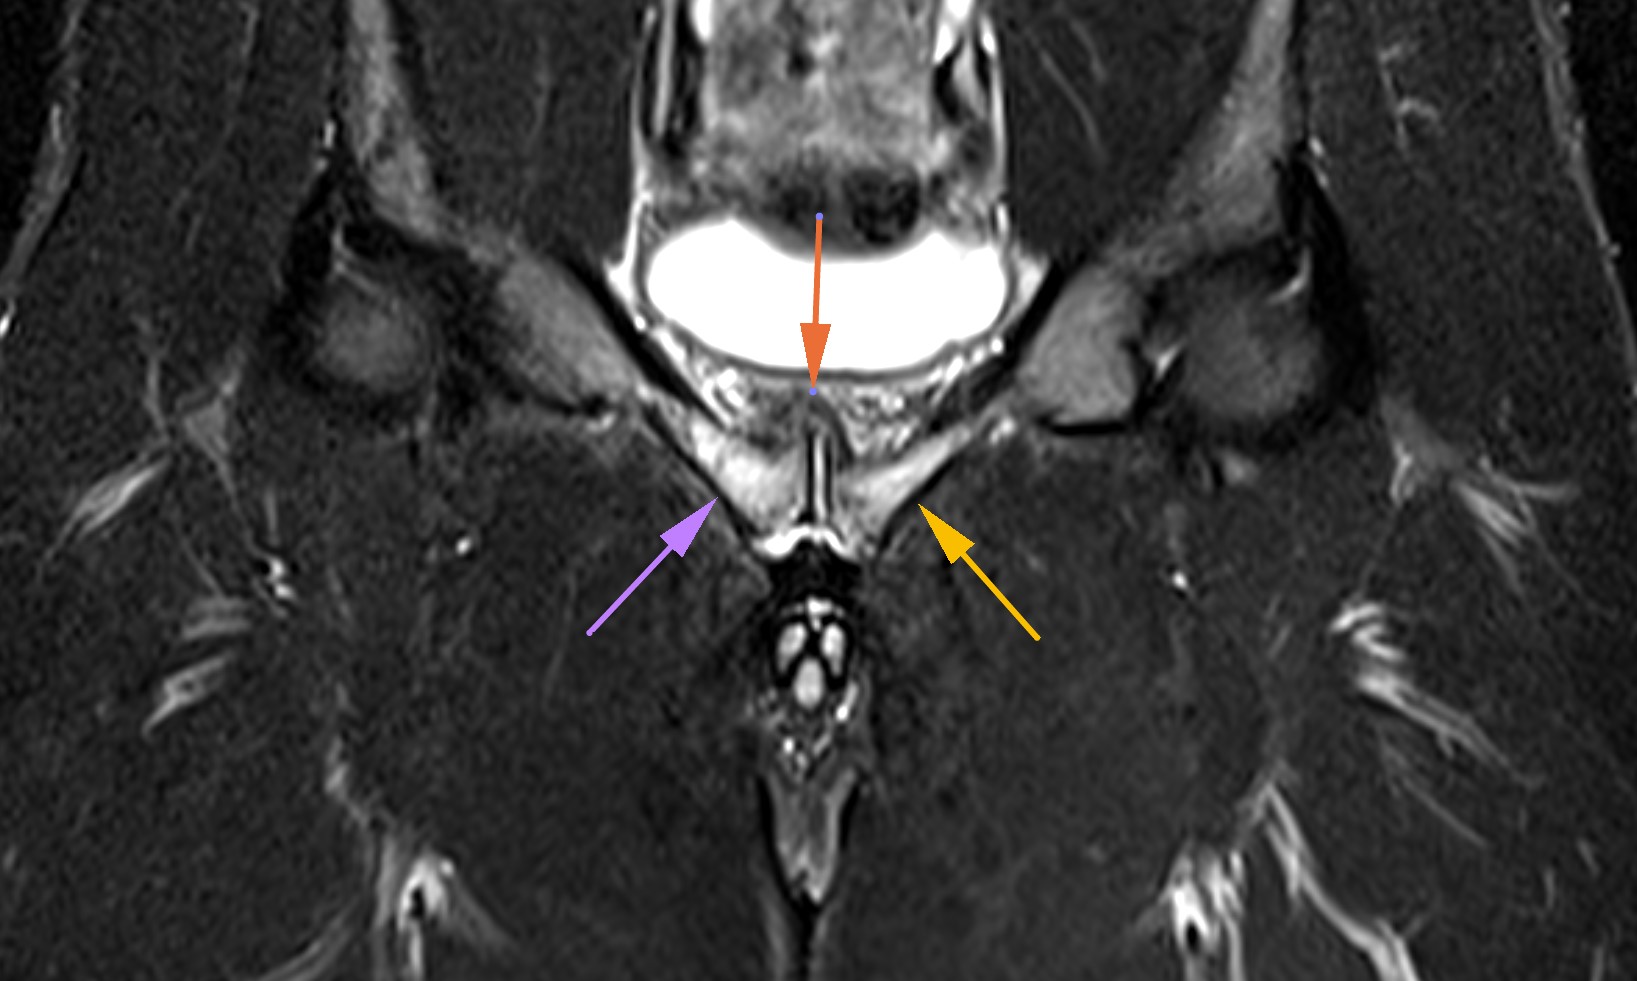

OSTEITIS PUBIS

One of the most common injuries in today’s sport is inflammation of the pubic bone. Injury has many different varieties and symptoms from inflammation of symphysis pubisgroin pain, adductor muscles strain, abdominal wall pain to inflammation of pelvis